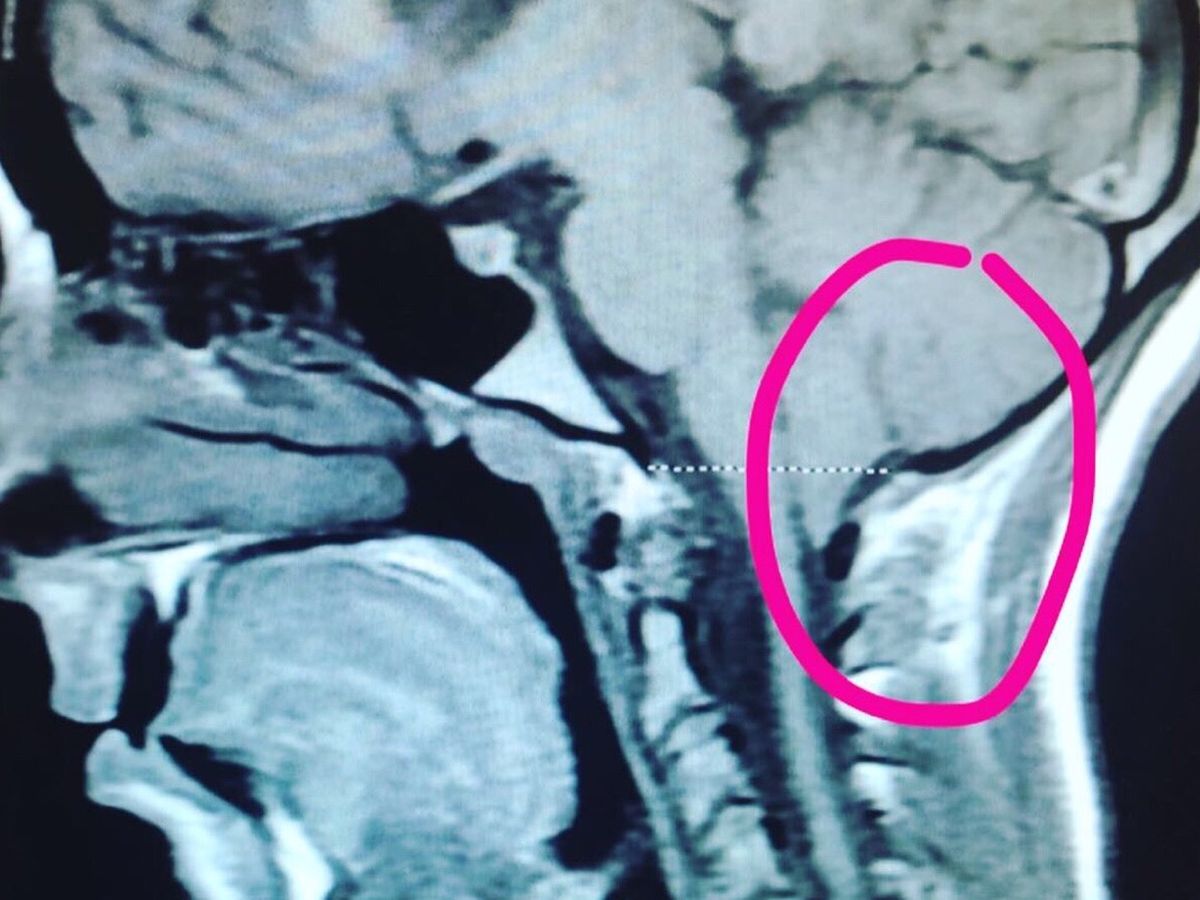

Chiari Malformation is “a problem in which a part of the brain (the cerebellum) at the back of the skull bulges through a normal opening in the skull where it joins the spinal canal. This puts pressure on parts of the brain and spinal cord.” I am scheduled to undergo decompression surgery in September, which happens to be Chiari Awareness Month, to remove the bone at the back of the skull and spine, and open the dura Mater. The dura overlying the cerebral tonsils is opened and a patch is sewn to expand the space, similar to letting out the waistband on a pair of pants. The goals of surgery are “to stop or control the progression of symptoms caused by tonsillar herniation, to relieve compression of the brainstem and spinal cord, and to restore the normal flow of cerebrospinal fluid (CSF).” The surgery takes about 2 to 3 hours and recovery in the hospital usually lasts 2 to 7 days!

Chiari Malformation is “a problem in which a part of the brain (the cerebellum) at the back of the skull bulges through a normal opening in the skull where it joins the spinal canal. This puts pressure on parts of the brain and spinal cord.” I am scheduled to undergo decompression surgery in September, which happens to be Chiari Awareness Month, to remove the bone at the back of the skull and spine, and open the dura Mater. The dura overlying the cerebral tonsils is opened and a patch is sewn to expand the space, similar to letting out the waistband on a pair of pants. The goals of surgery are “to stop or control the progression of symptoms caused by tonsillar herniation, to relieve compression of the brainstem and spinal cord, and to restore the normal flow of cerebrospinal fluid (CSF).” The surgery takes about 2 to 3 hours and recovery in the hospital usually lasts 2 to 7 days!